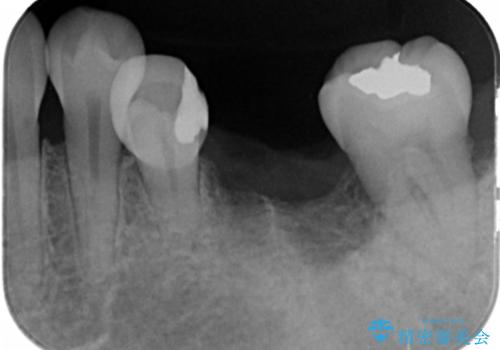

昔神経の治療をした歯が割れてしまっていました。

やむなく抜歯になりましたが、その部分にインプラントを始め希望されましたが、炎症により、骨がなく、かつ歯並びの関係で入れても歯ブラシができずにインプラントも長くもたなそうという診断になりました。

インプラントではなくブリッジにするためには、奥歯の並びを矯正しておいた方がいい状態でした。